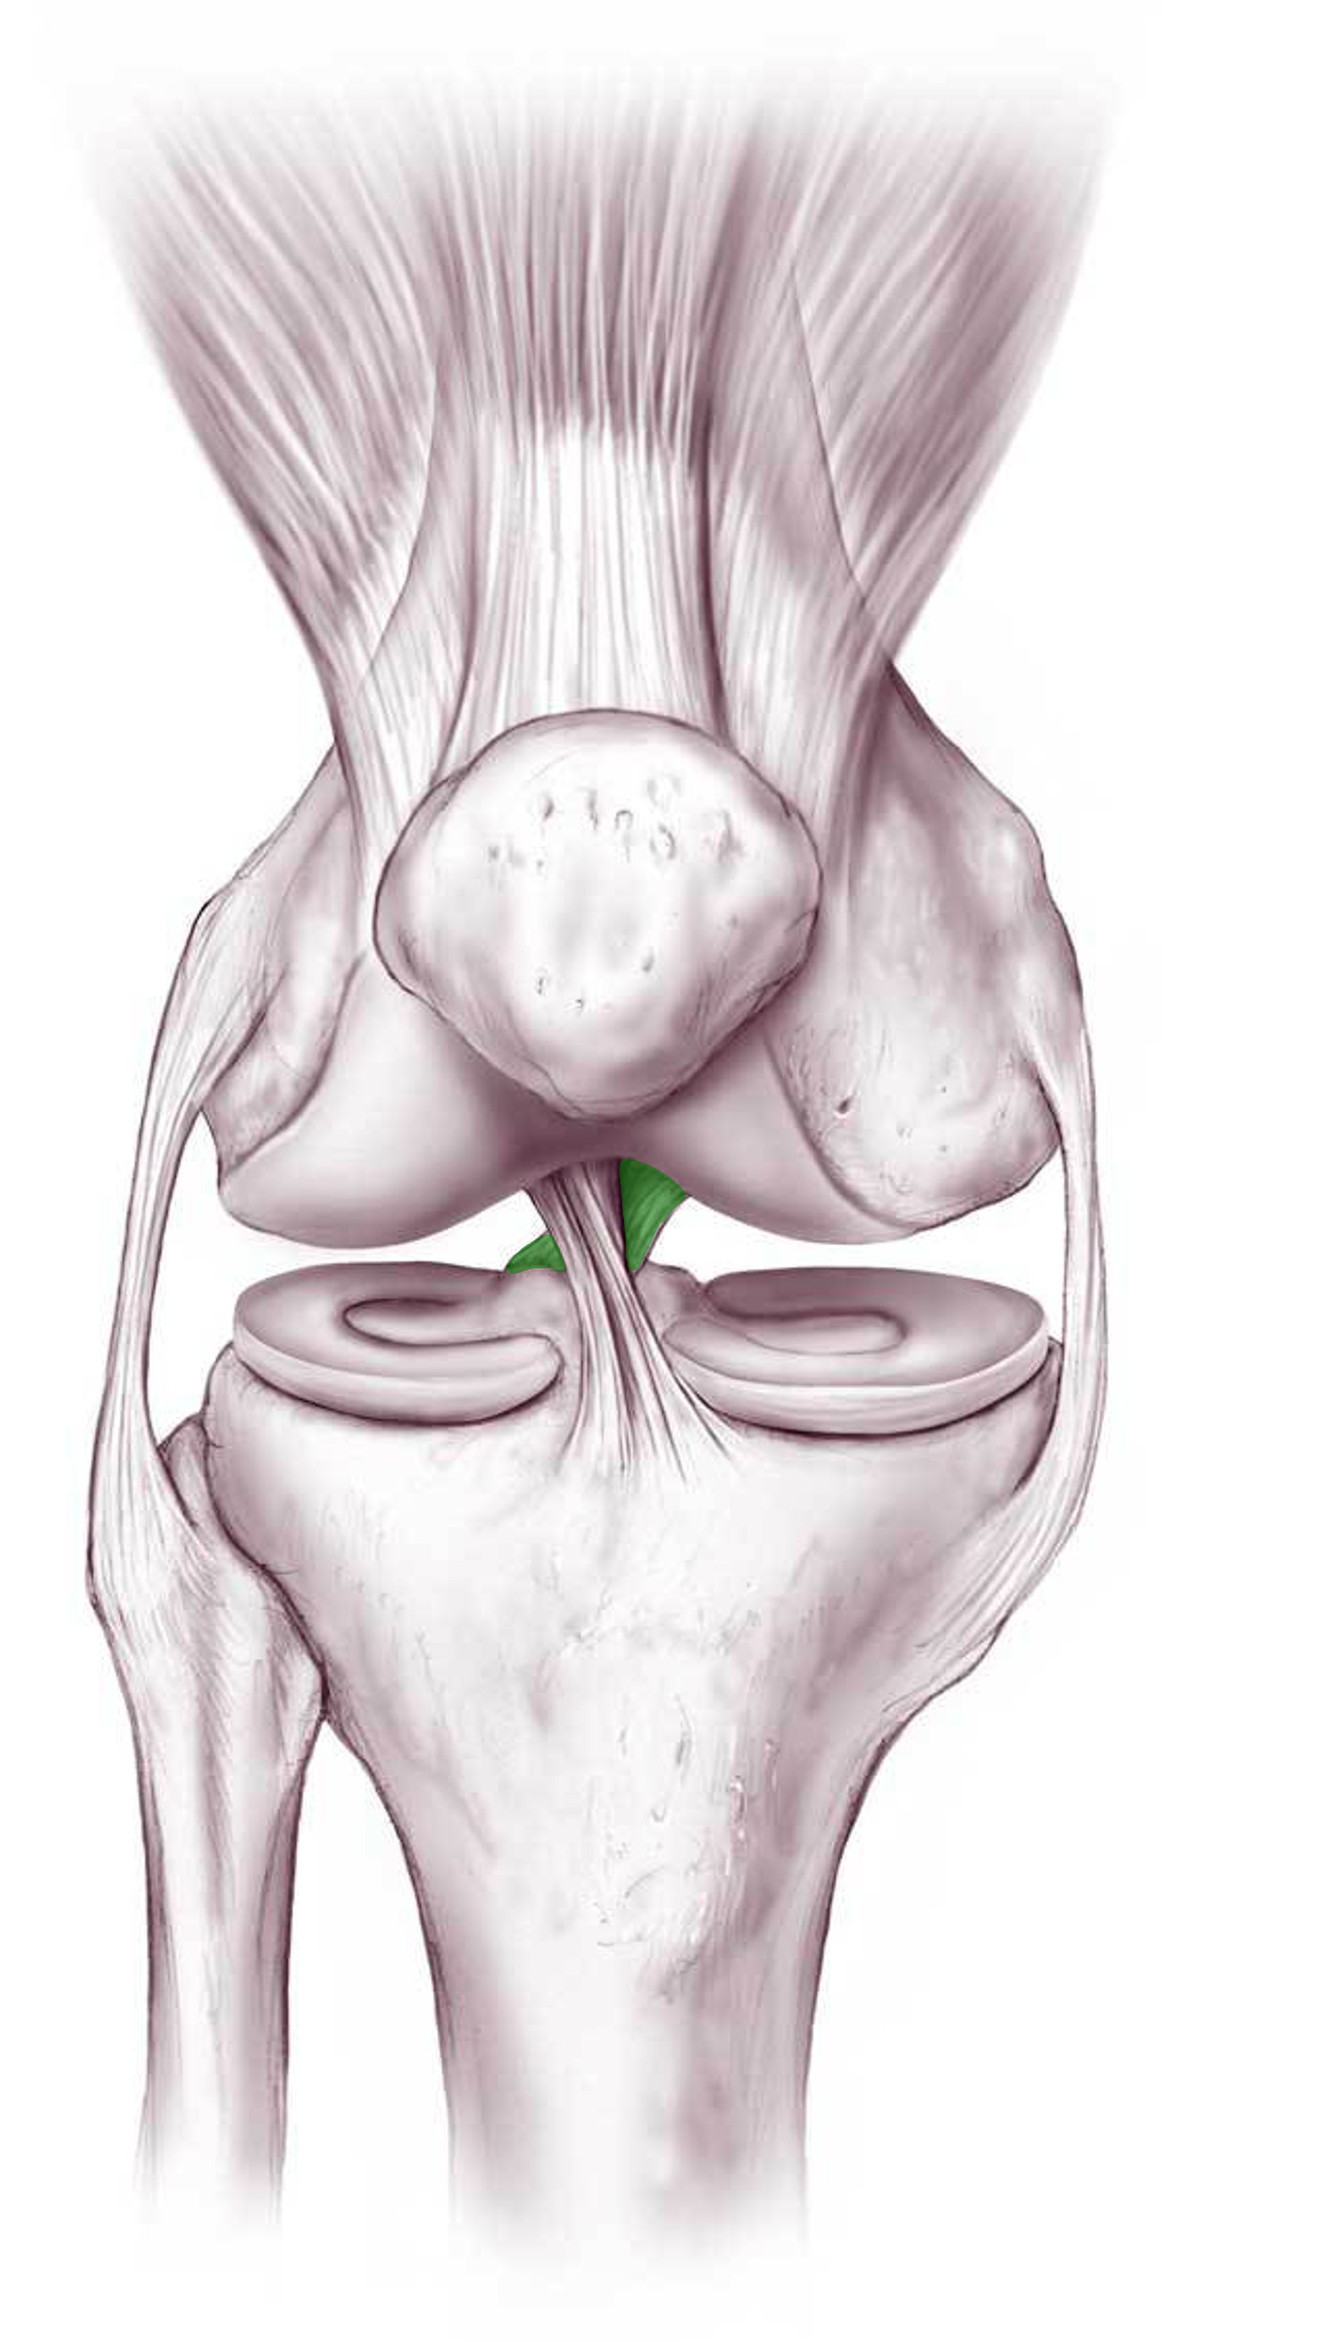

What is this structure?

Posterior cruciate ligament of the knee

What is the function of this structure?

Posterior cruciate ligament of the knee

Prevents femur from sliding posteriorly on tibia